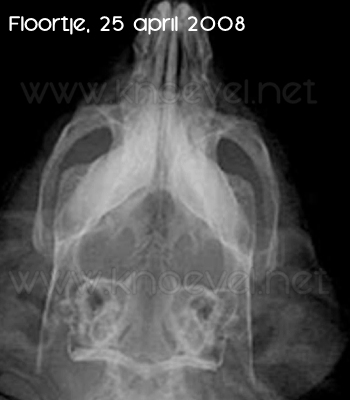

De foto’s die van Lynn werden gemaakt, gaven een duidelijk beeld: gaten in de kniegewrichten, afwijkingen aan het bot van de kaken. De diagnose: OD……. Hoewel Floortje (toen 1,5 jaar oud) nog geen klachten liet zien, waren ook haar foto’s waren duidelijk: beginnende OD. Viggo van Stein is mijn derde satijncavia, geboren juni 2007, bij mij sinds maart 2008. Ook van hem zijn foto’s gemaakt; gelukkig zijn er bij hem geen afwijkingen te zien.

De röntgenfoto’s van de drie, die in april 2008 zijn gemaakt, zijn onderaan dit verhaal te zien.

Op 31 oktober 2008 zijn mijn drie satijntjes weer onderzocht door dierenarts Krista Caers en werden er ook weer röntgenfoto’s gemaakt, precies een half jaar na de eerste reeks.

Helaas…………….wat de dierenarts al voelde bij het onderzoek bleek ook uit de foto’s: Lynn’s foto laat heel duidelijk zien dat er een behoorlijke verslechtering is van de toestand van haar knieën en haar kaken. Geen gebitsproblemen, geen andere zaken, maar dus wel een ernstiger OD.

Goed nieuws was er voor Floortje, die niet verder achteruitgegaan is in het afgelopen halfjaar (voor alle duidelijkheid: Floortje heeft geen BIS gekregen).

Nog beter nieuws is er voor Viggo, die met zijn 1,5 jaar geen tekenen van OD vertoont!

Jammer genoeg is bij Lynn van een positief effect van dit medicijn geen enkele sprake – kijk maar naar de foto’s van 31 oktober 2008, die hieronder staan.

Tenslotte de röntgenfoto’s van de drie satijntjes: